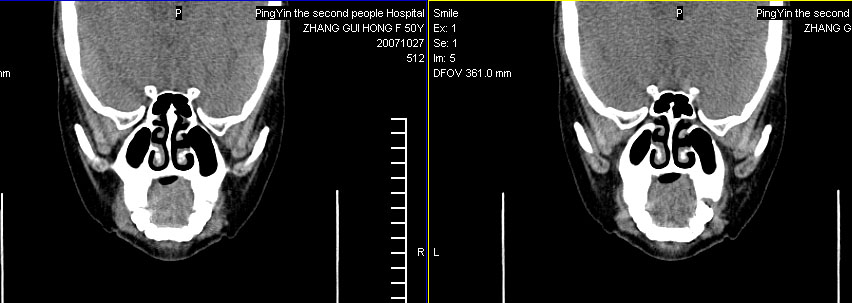

标题: CT10219:蝶鞍区有无异常?

女。50岁.头疼恶心半月余.双上颌窦区压疼明显,曾有高血压.现基本控制.

有问题,双侧侧脑室扩大,感觉鞍区有肿块,建议增强扫描.

感觉鞍区异常,建议增强扫描.